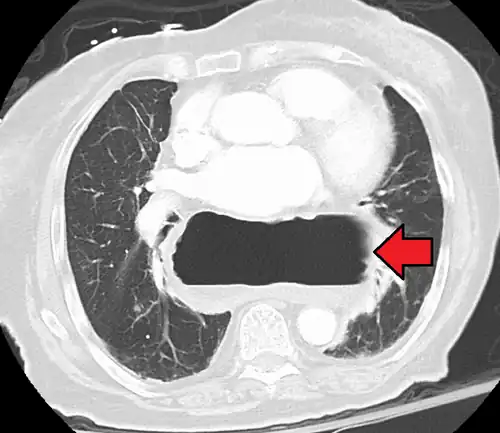

This hiatal hernia is mainly identified by an air-fluid level (labeled with arrows). -